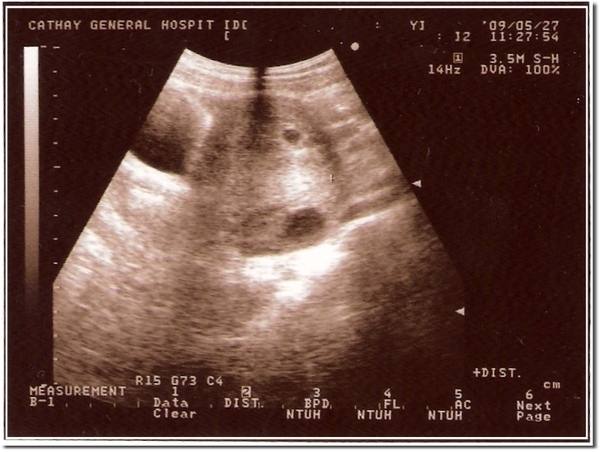

就在搬完家後跟醫生約了時間趕快去醫院確定一下

醫師直接幫我照肚皮超音波

98/05/27 第一次照超音波,大約5週多

還很小,不過確定是已經懷孕囉

980527.jpg